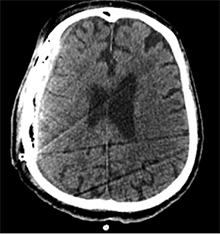

Praėjus dar 2 sav., pacientas iš slaugos ligoninės atvežtas dėl vangumo, dezorientacijos, nerišlios ir sulėtėjusios kalbos. Atlikus GKT, dešinėje pusėje po kraniotomijos lopu įtarta poūmė (ūmi) epidurinė hematoma, nesant VSD. Per parą pacientas operuotas. Operacijos metu po minkštaisiais audiniais rasta kraujo sankaupa su seroziniu komponentu, paimtas bakteriologinis pasėlis. Po KPL rasta krešulių su skystu krauju ir seroziniu komponentu. Paimtas antras bakteriologinis pasėlis, įtariant infekciją. Hematoma (seroma) pašalinta. Žaizda plauta mažos koncentracijos betadinu ir fiziologiniu tirpalu. Kraujavimo iš KSD nepastebėta. Nuspręsta KPL grąžinti – labiau tikėtina epidurinės seromos (EDS) diagnozė. Siekta uždaryti „negyvąjį“ epidurinį tarpą, pakabinant KSD centre prie KPL siūlais, tačiau KSD buvo nepaslankus, tampriai priaugęs prie smegenų. Atlikus kontrolinę GKT (9 pav.), nustatyta teigiamų pooperacinių pakitimų, smarkiai sustorėjęs KSD, tarpas tarp KPL ir KSD. VSD nenustatyta. Po operacijos paciento bendroji būklė buvo stabili. Reakcija buvo kiek sulėtėjusi, tačiau vyras gebėjo atsakyti į elementarius klausimus. Teigiama klinikinė dinamika. Po savaitės pacientas tapo labai vangus, sulėtėjo, skundėsi silpnumu, kalbėjo nesklandžiai. Pakartojus GKT (10 pav.), nustatyta padidėjusi epidurinė skysčio sankaupa, panaši į mišraus tankio hematomą (apie 64 ml tūrio) dešinėje pusėje frontotemporoparietaliai, padidėjusi VSD į kairę – iki 4 mm. Kadangi pacientas per tą patį randą jau operuotas 6 kartus, o po operacijų pastebimos vis atsinaujinančios pakartotinės EDS, priimtas sprendimas neskirti operacinio gydymo. KPL turėjo daugybinių perforacijų, todėl nuspręsta atlikti subgalinio tarpo punkciją, tikintis, kad per perforacijas išbėgs EDS. Atlikus punkciją, gauta 20 ml serohemoraginio skysčio. Po procedūros paciento būklė pagerėjo, jis tapo kiek aktyvesnis, tačiau efektas nebuvo patenkinamas. Kitą dieną nuspręsta punktuoti pakartotinai, gauta 4 ml serohemoraginio skysčio. Tūris buvo nepakankamas teigiamam efektui gauti. Priimtas sprendimas skirti lašinių infuzijų ir švelnią osmoterapiją neurologinei simptomatikai sumažinti. Punkcijos nedavė norimo efekto, todėl nuspręsta suformuoti poodinę neigiamo slėgio drenažinę sistemą po minkštųjų audinių lopu. Į subgalinį tarpą įvestas 20G periferinės venos kateteris, fiksuotas prie odos ir sujungtas su uždara vakuumine sistema, tikintis nuolatinio drenavimosi smegenų kompresijai sumažinti. Per 5 lovadienius išsiskyrė apie 50 ml serohemoraginio skysčio. Atlikus kontrolinę GKT, buvo matyti teigiama dinamika (11 pav.). Dėl infekcijos profilaktikos vakuuminė sistema pakeista 2 kartus. Įvedus vakuuminę sistemą, po 12 lovadienių paciento būklė pagerėjo, jis tapo aktyvesnis, į klausimus atsakydavo prasmingai, paliepimus vykdydavo visomis galūnėmis. Vakuuminė sistema pašalinta. Po 2 dienų atlikta GKT (12 pav.). EDS dešinėje pusėje regresavo, smegenų kompresijos nenustatyta. Esant stabiliai būklei ir teigiamai dinamikai, pacientas grąžintas į slaugos ligoninę.

9 pav. Po šeštosios operacijos (teigiami pooperaciniai pakitimai, smarkiai sustorėjęs kietasis smegenų dangalas, tarpas tarp kaulo ir kietojo smegenų dangalo; VSD nėra)